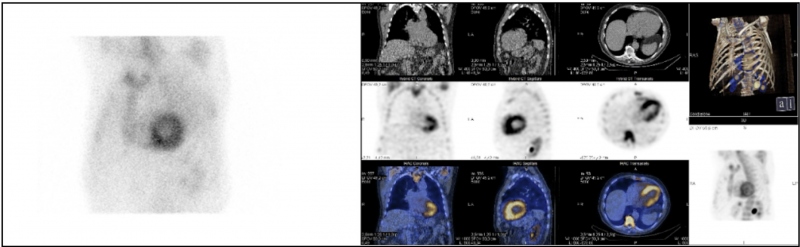

Se realizó una cardio-resonancia magnética (CRM), la cual informó de hallazgos compatibles con miocardiopatía infiltrativa, planteando como primera posibilidad amiloidosis cardíaca (Fig. 1). Finalmente, la gammagrafía con 99mTc-HDP y SPECT/TC torácico reveló captación del radiotrazador por parte de ambos ventrículos, de carácter difuso y grado 3 en la escala de Perugini, siendo estos hallazgos altamente sugestivos de afectación por amiloidosis cardíaca por acúmulo de transtirretina (TTR)(1,2,3) (Fig. 2).